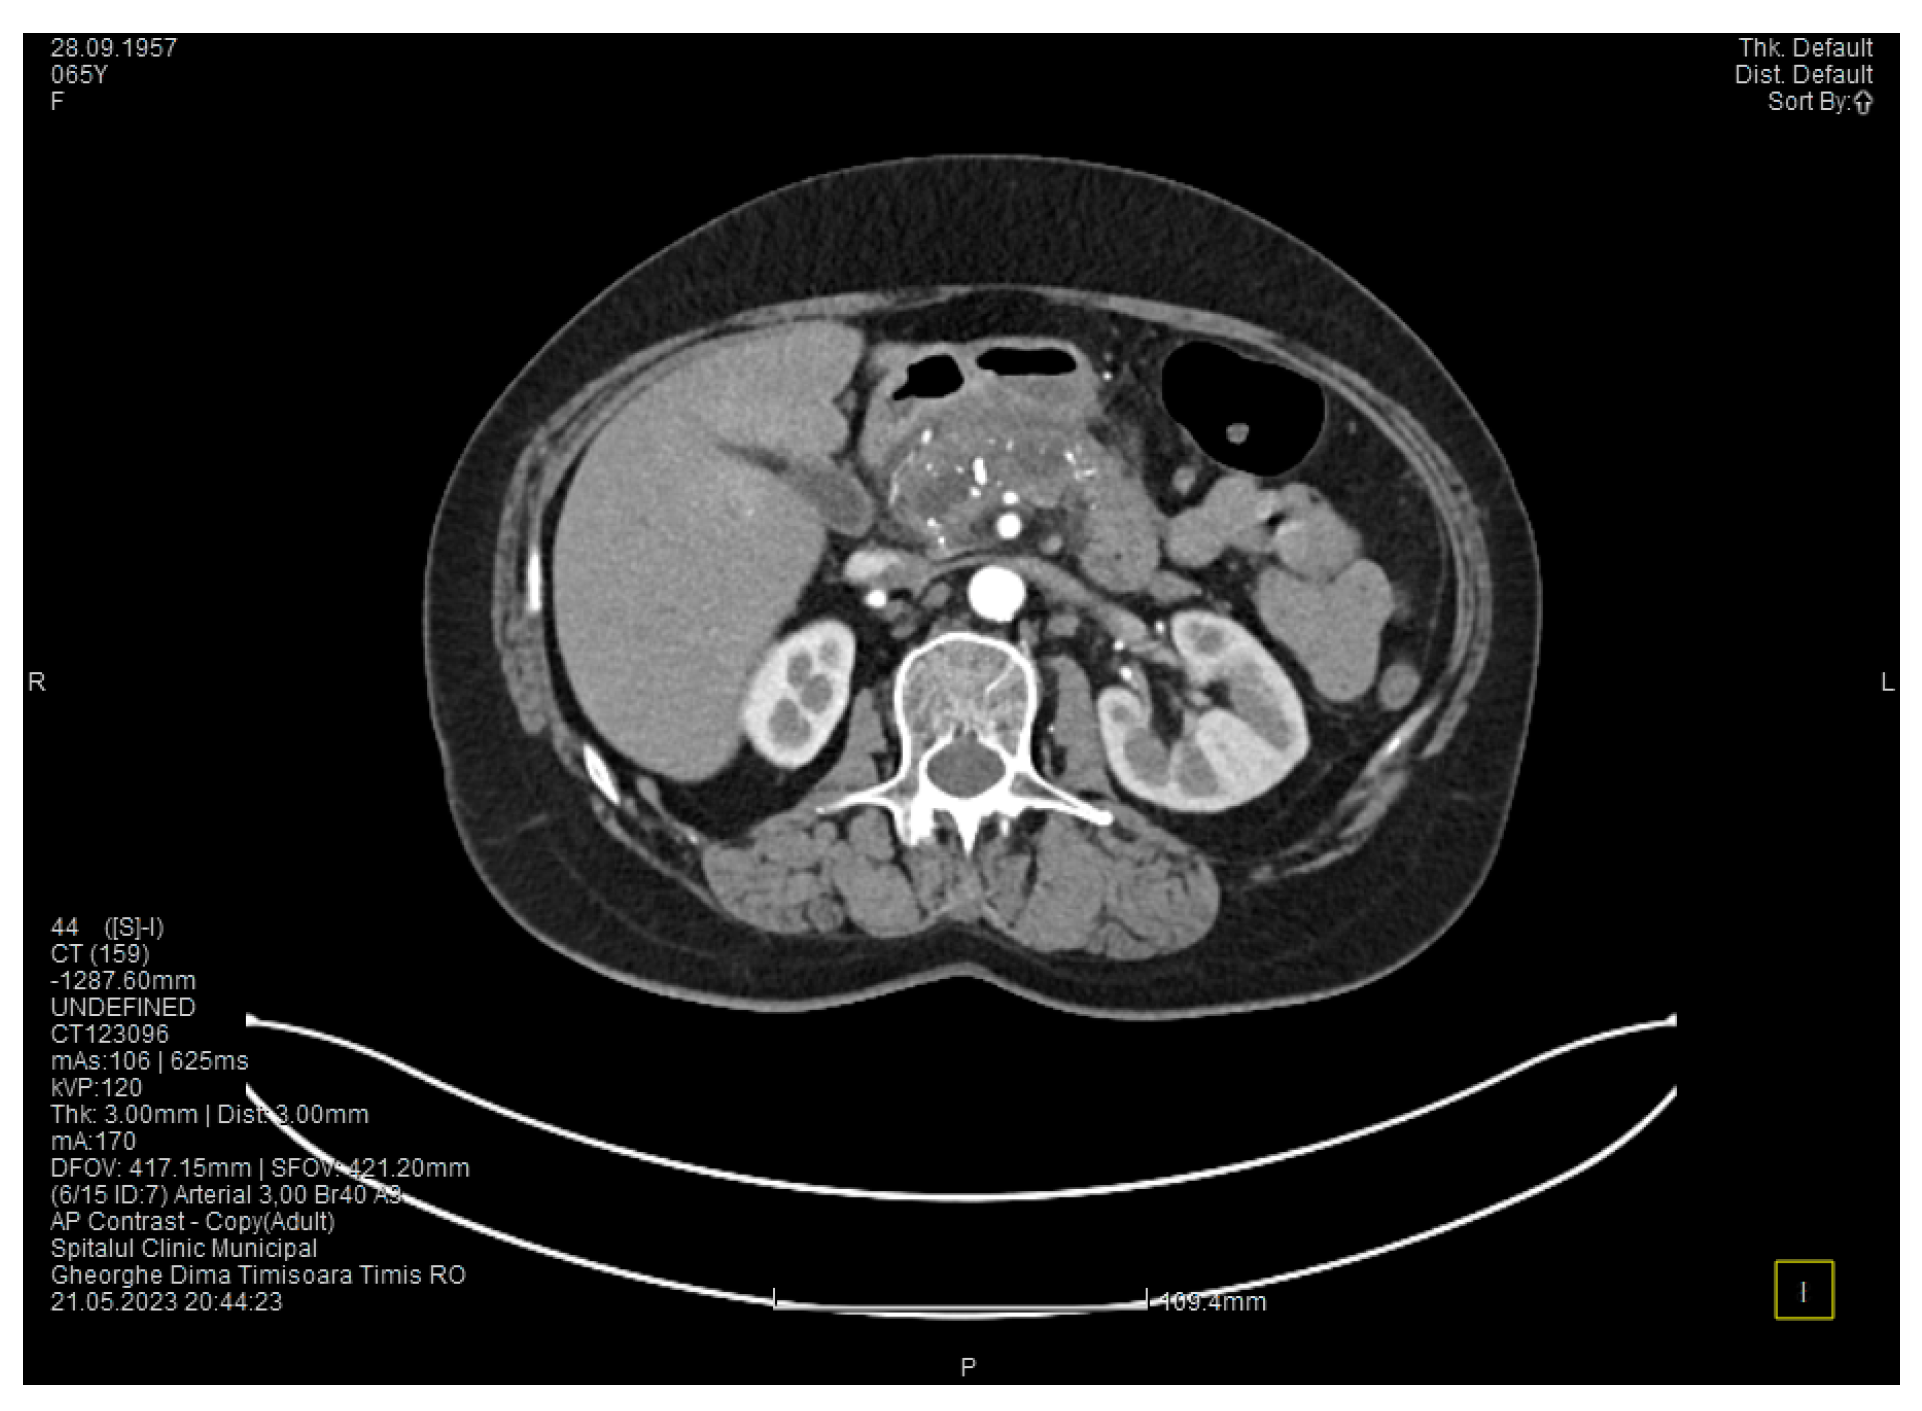

Laboratory tests showed a serum lipase level more than 10 times above the upper normal range. The contrast-enhanced computed tomography (CT) showed multiple calcifications in the pancreatic tissue, dilatation of the main pancreatic duct measuring approximately 12.5 mm (Figure 1), a non-iodophilic intraparenchymal cyst in the head of the pancreas measuring 23/25 mm, which was associated with acute inflammation (Figure 2), and densification of the peripancreatic fat, which was more intense at the head of the pancreas. In addition, enlarged pericephalic and periaortocaval lymph nodes were observed. There were no changes in the liver or the gallbladder, only a mild ectasia of the intrahepatic bile ducts, and no dilatation of the common bile duct. Other changes included multiple atheromas of the abdominal aorta. The symptoms, the lab results, and the CT findings led to the diagnosis of acute pancreatitis.

Figure 1. The initial CT scan shows a dilated Wirsung duct and calcifications in the pancreatic tissue.